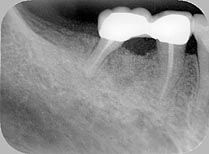

3.X線片 需要標準投照技術才能進行術前和術後的比較,但仍有誤差。